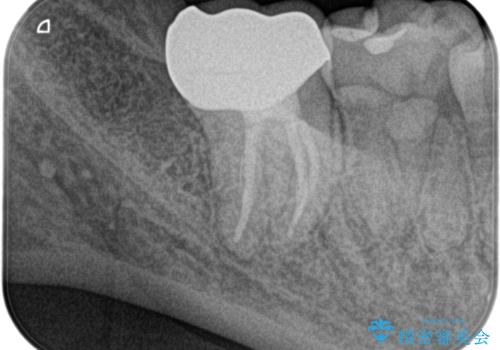

- 精密根管治療(イニシャルケース,大臼歯):122,000円、ファイバーコア:22,000円、オールセラミッククラウン (スタンダード):110,000円、仮歯:11,000円費用は治療当時の料金となります

根管治療後は速やかに歯冠修復が必要です。